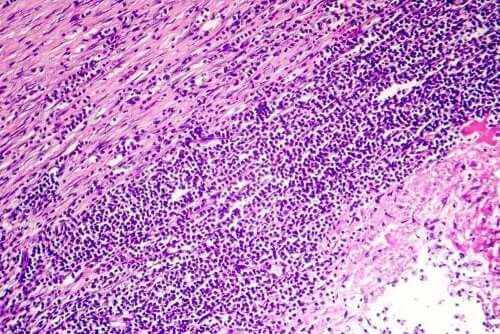

약 80%의 사례에서 심낭염의 원인을 규명하는 것은 불가능하다. 하지만, 염증의 시작이 특정 감염의 결과인 것은 매우 흔하며, 바이러스 감염일 가능성이 매우 높다. 세균 감염은 있을 수 있지만 그 정도는 덜하고, 아주 드물게 곰팡이 감염이 원인일 수 있다.